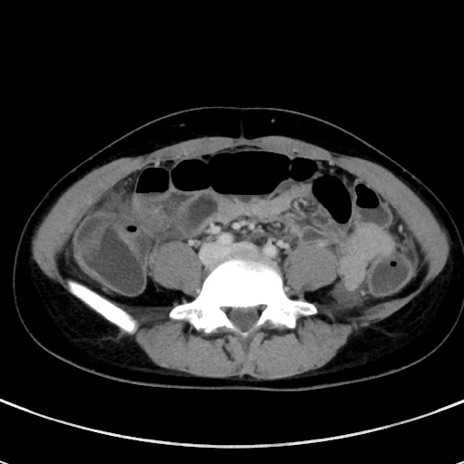

症例17(横断像)

【症例】20歳代女性

【主訴】嘔吐、下腹部痛

【現病歴】昨日夕食後に嘔吐し下腹部痛が出現。本日になっても嘔吐持続し改善しないため来院。

【身体所見】意識清明、BT 37.2℃、BP 108/67mmHg、腹部:平坦、やや硬、下腹部正中から右にかけて圧痛あり、反跳痛軽度あり、tapping pain(+)。

【データ】WBC 13600、CRP 14.94